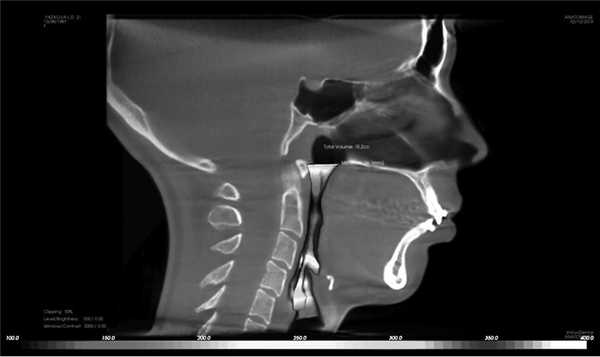

В статье представлен подробный протокол конусно-лучевой компьютерной томографии (КЛКТ), включающий не только классический анализ зубоальвеолярных и скелетных нарушений, но и диагностику краниальных паттернов (краниоцервикальный цефалометрический анализ по M. Rocabado, данные цефалометрической диагностики по Sassouni PLUS), анализ трансверзальных размеров челюстей (Penn анализ), а также измерение объема дыхательных путей для скрининга обструктивного апноэ. Обзор литературы был проведен с использованием поисковой системы PubMed в электронных базах данных Scopus и Medline по апрель 2020 г. Сделан вывод, что совмещение в едином протоколе нескольких методик интерпретаций КЛКТ позволит врачам получить более полный объем информации для составления полноценного плана комплексного лечения.

Дата принятия в печать:

III. Анализ краниомандибулярных нарушений (необходим при планировании комплексного лечения совместно с миофункциональным терапевтом) и оценка объема дыхательных путей для исключения синдрома обструктивного апноэ. Оценка положения подъязычной кости (краниоцервикальный цефалометрический анализ по M. Rocabado) и языка. Измерение проводится следующим образом: необходимо провести линию от передненижнего угла тела III шейного позвонка к наиболее нижней точке подбородочного симфиза Me (Menton), далее к начерченной линии проводят перпендикуляр от наиболее передней и верхней точки подъязычной кости. В норме длина перпендикуляра должна составлять 5,0±2,0 мм (рис. 6).

Рис. 6. Подъязычный треугольник по M. Rocabado (а) и оценка положения подъязычной кости к основанию тела нижней челюсти (0,09 мм) (б).

2. Дыхательные пути. В программе имеется визуальная шкала оценки степени сужения верхних дыхательных путей на уровне носо- и ротоглотки, основанная на исследовании David Hatcher. В норме площадь поперечного сечения дыхательных путей составляет 110—140 мм 2 . Объем дыхательных путей в данной программе рассчитывается от анатомической точки PNS до надгортанника. Черный, красный и оранжевый цвета обозначают сужение дыхательных путей (рис. 7) [10].

Рис. 7. Сужение дыхательных путей. Минимальная площадь поперечного сечения 26,1 мм 2 (норма 110—140 мм 2 ).

В норме язык должен занимать весь свод твердого неба; если на КЛКТ прослеживается пространство между языком и твердым небом, то это свидетельствует о неправильном его положении и функции, из-за чего происходит сужение дыхательных путей на уровне ротоглотки [11].